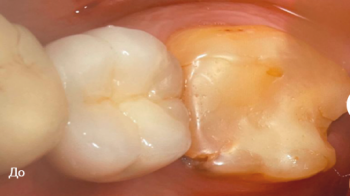

2 работы в портфолио